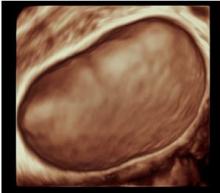

In seguito a questo grande impegno che sta continuando con il reclutamento di nuovi centri e di nuovi casi, ormai vi è in letteratura una forte evidenza che la valutazione soggettiva di una massa ovarica effettuata da un operatore dedicato attraverso l'ecografia sia un ottimo metodo per discriminare tra benignità e malignità ed in molti casi può essere suggerita pure una corretta diagnosi di natura della neoplasia sulla base della sola ecografia che, se associati alla clinica, all'esecuzione dei marcatori ovarici, aumentano ulteriormente la sensibilità nella diagnosi e nella stadiazione preoperatoria.

I progetti in essere prevedono l'esecuzione di ecografie ginecologiche di II livello di un operatore dedicato, atte a discriminare tra patologia benigna e maligna ovarica secondo la caratterizzazione della massa con i dati dello IOTA.

L’expertise dell’operatore, associato all’acquisizione da parte dell’Istituto di un’apparecchiatura di alto livello, dotata di software di ultima generazione anche con 3D e 4D, permettono di caratterizzare nei minimi dettagli l’eventuale presenza di patologia ovarica e di verificare l’eventuale disseminazione limitrofa agli organi circostanti. Questo da una parte dovrebbe permettere di evitare di misconoscere o sottovalutare alcune patologie ovariche potenzialmente evolutive in senso maligno e pertanto da indirizzare a trattamento chirurgico, e dall'altra di condurre un follow-up ecografico ad alcune patologie ovariche definite benigne secondo criteri standardizzati e ampiamente validati atti ad evitare una chirurgia non necessaria. Nel gruppo di lavoro IOTA infatti si è visto in questi anni che quasi l'80 percento delle masse ovariche operate risultavano benigne. E’noto che ogni procedura chirurgica è associata a possibili complicanze a breve come a lungo termine.